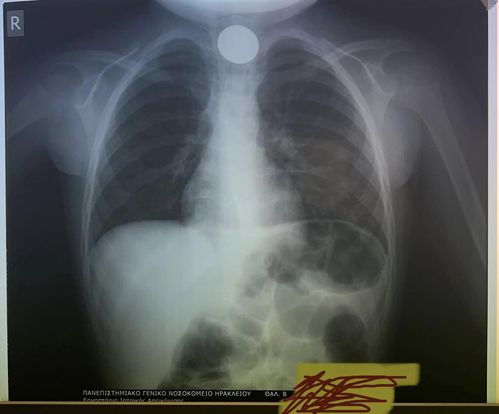

Εσπευσμένα στο νοσοκομείο Ηρακλείου μεταφέρθηκε παραμονή Πρωτοχρονιάς ένα παιδί μόλις 4 χρονών, το οποίο είχε καταπιεί ένα κέρμα και δεν μπορούσε να αναπνεύσει.

- Σύμφωνα με πληροφορίες του cretapost, αμέσως οδηγήθηκε στο νοσοκομείο με τους γιατρούς να προχωρούν σε επείγουσα αφαίρεση η οποία στέφθηκε με επιτυχία.